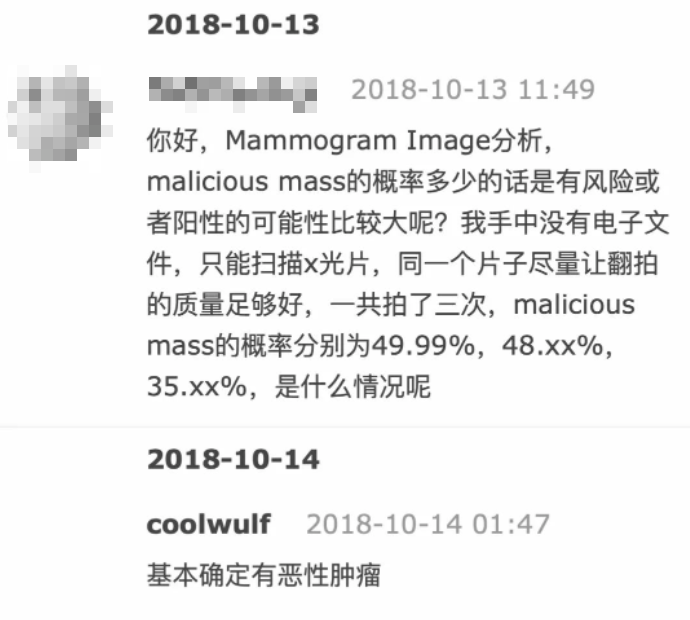

他说,由于后台不保存数据,所以并不清楚具体有多少人使用过。

但在那段时间,他收到了很多患者的感谢邮件,不少都来自国人。

而且,用户真的用网站检查出了肿瘤,尤其对于医疗资源紧张地区的人们,相当于从死神手里抢下时间。

第一位哥们照片搞错了,

重新检测后发现了肿瘤 ▼